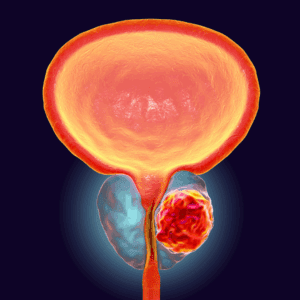

El cáncer de próstata se desarrolla cuando las células de la glándula prostática comienzan a crecer sin control. Lo complejo es que, en sus primeras etapas, no presenta síntomas evidentes. Con el avance de la enfermedad, pueden aparecer señales como dificultad para orinar, sangre en la orina o el semen, dolor pélvico o disfunción eréctil.

Una enfermedad silenciosa, pero prevenible

La clave para reducir la mortalidad por cáncer de próstata es la prevención. La tasa de recuperación varía de acuerdo con la etapa en que se diagnostica el cáncer y su nivel de agresividad. Según el doctor Caiceo: “En términos generales, cuando se detecta en etapas iniciales, puede tener de un 85 a 90% de probabilidades de que el paciente se encuentre libre de enfermedad a los 5 años. Las secuelas van a depender también de muchos factores y de qué tratamiento se realizará el paciente, pero las principales secuelas son impotencia e incontinencia urinaria, que de todos modos se presentan en un bajo porcentaje.”